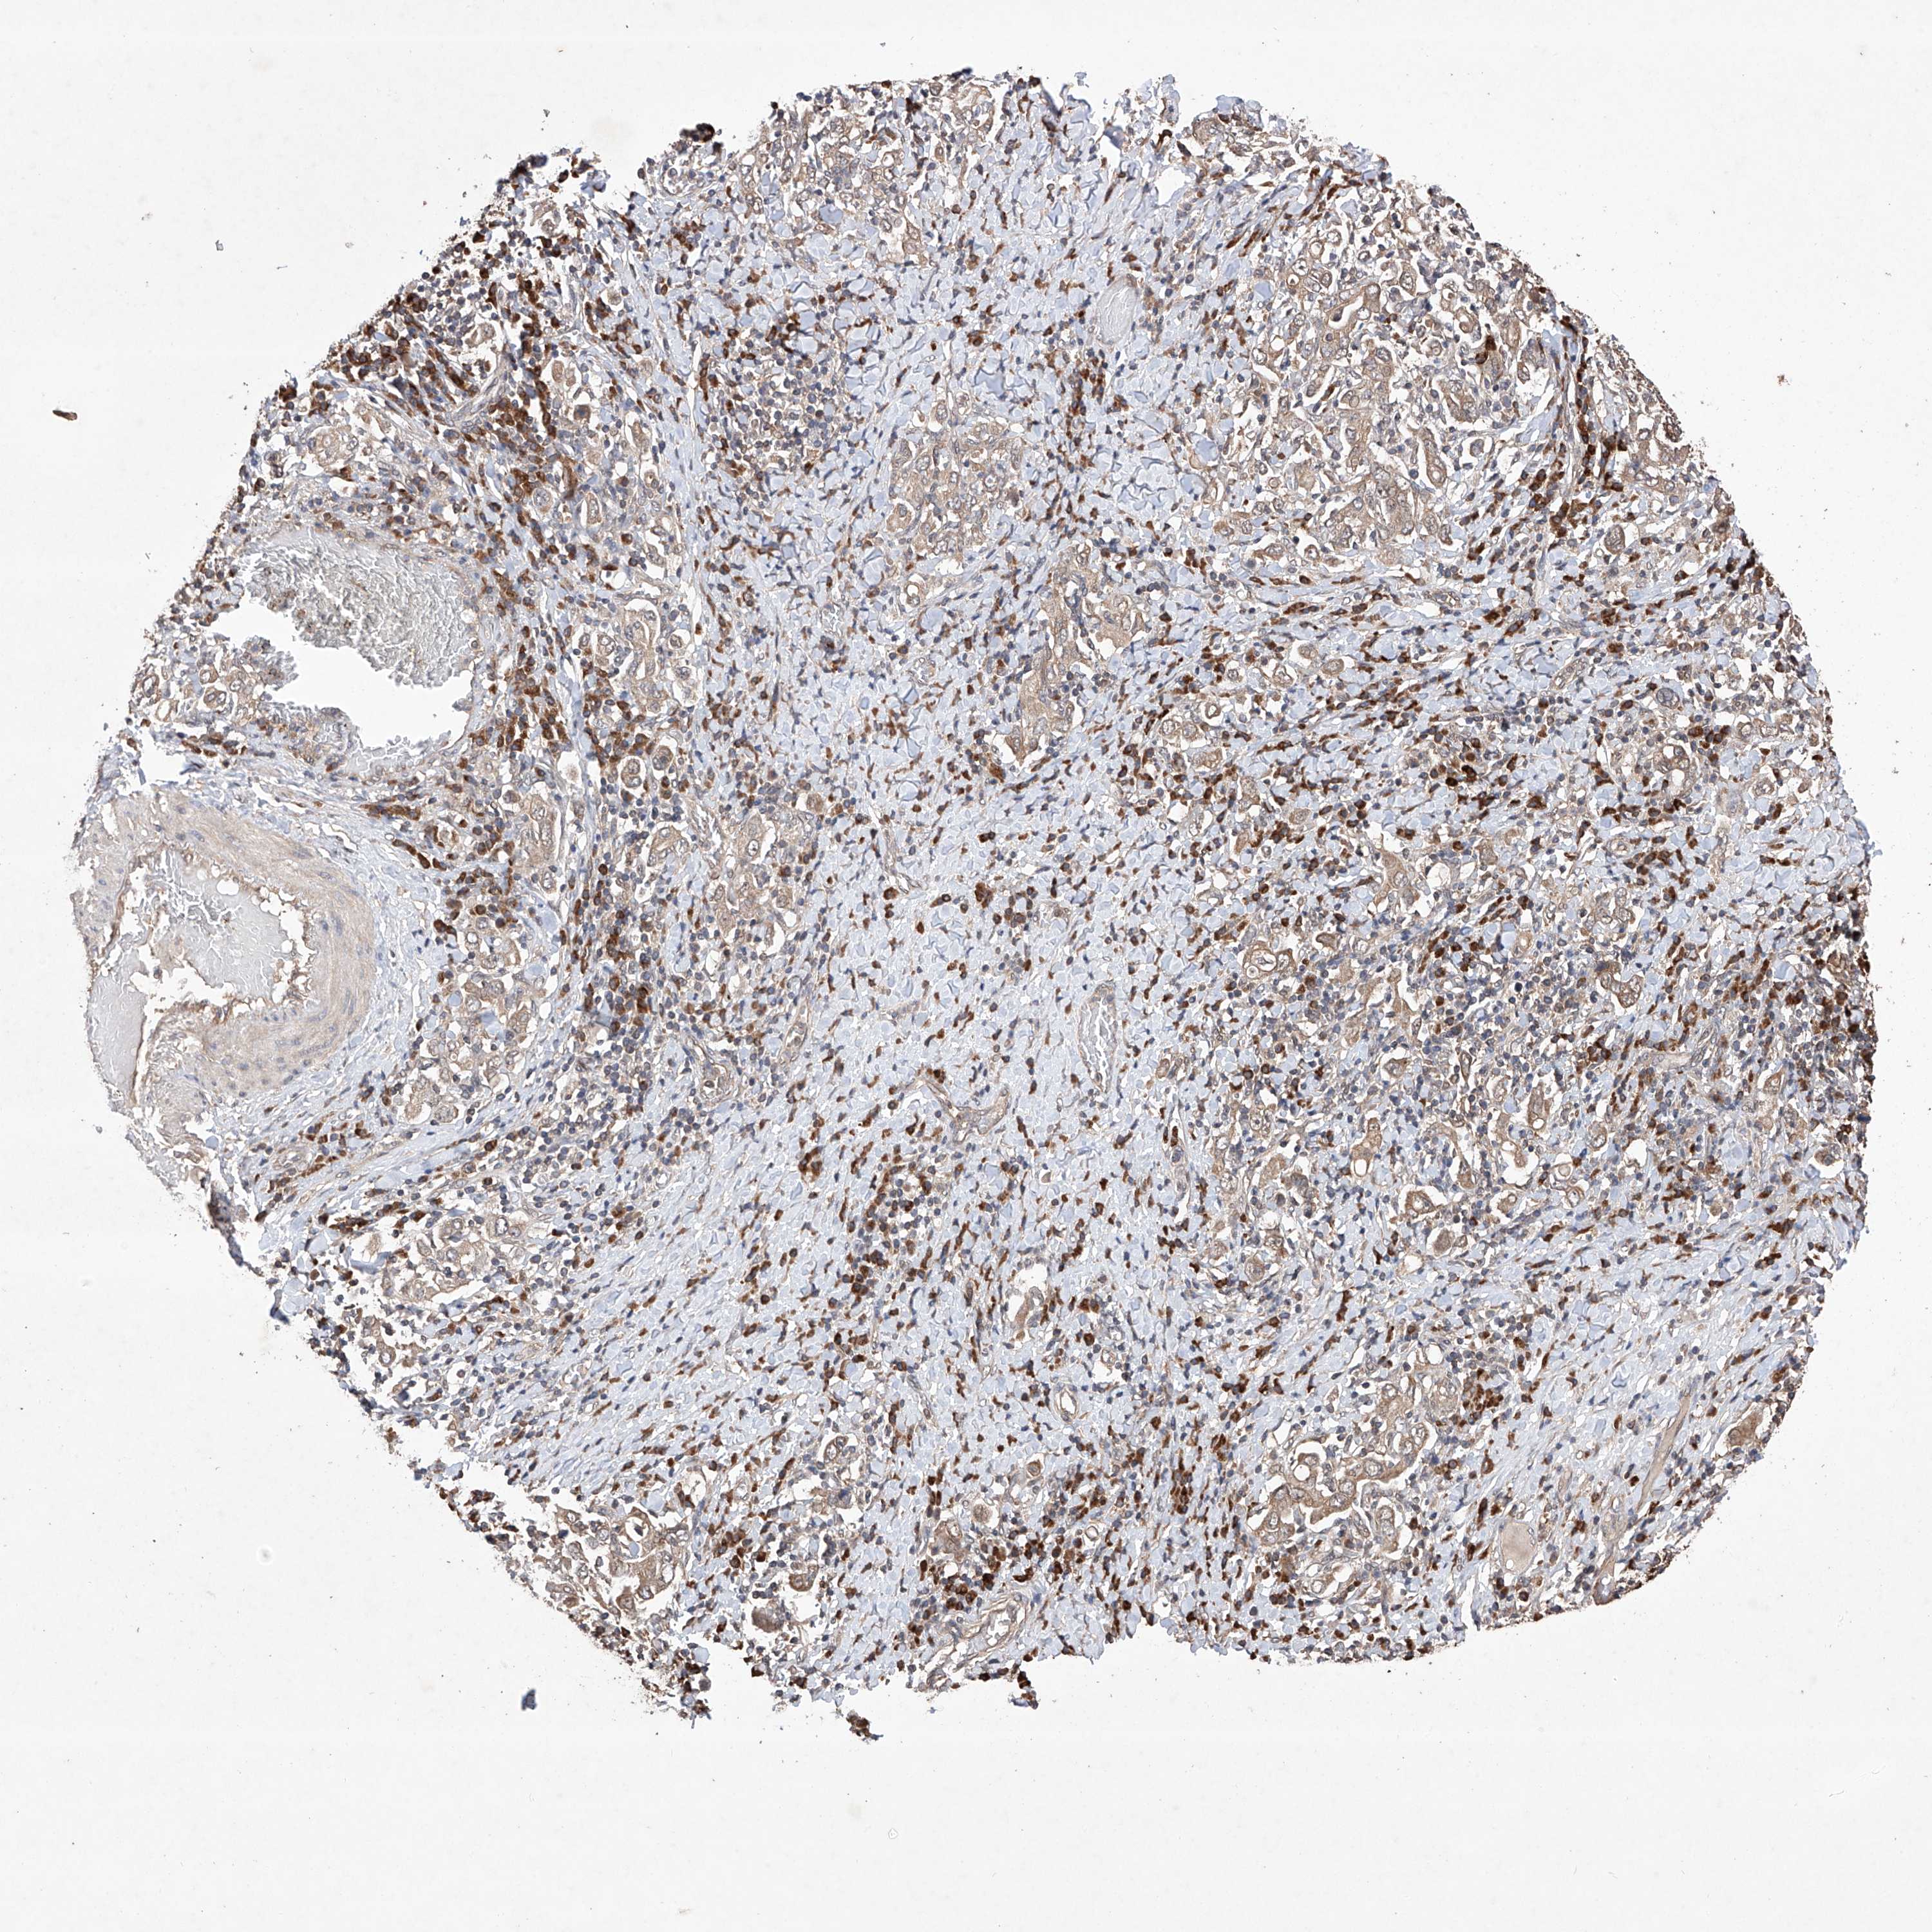

STOMACH CANCER - Protein expressioni

A mouse-over function shows sample information and annotation data. Click on an image to view it in a full screen mode. Samples can be filtered based on level of antibody staining by selecting one or several of the following categories: high, medium, low and not detected. The assay and annotation is described here.

Note that samples used for immunohistochemistry by the Human Protein Atlas do not correspond to samples in the TCGA dataset.

Antibody stainingi

Antibody staining in the annotated cell types in the current human tissue is reported as not detected, low, medium, or high, based on conventional immunohistochemistry profiling in selected tissues. This score is based on the combination of the staining intensity and fraction of stained cells.

Each image is clickable and will lead to virtual microscopy that enables deeper exploration of all samples and also displays staining intensity scores, fraction scores and subcellular localization as well as patient and tissue information for each sample.

Antibody HPA030060

Antibody HPA030061

Staining

High

Medium

Low

Not detected

Intensity

Strong

Moderate

Weak

Negative

Quantity

>75%

75%-25%

<25%

None

Location

Nuclear

Cytoplasmic/membranous

Cytoplasmic/membranous,nuclear

Adenocarcinoma, NOS